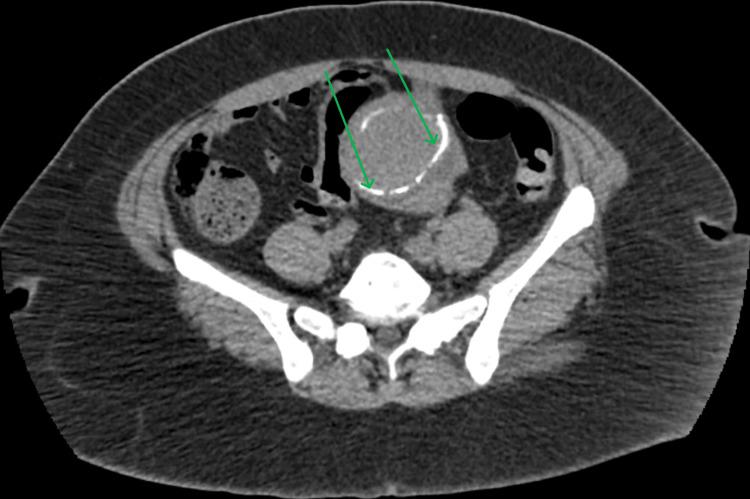

Tattoo-related infections are typically caused by gram-positive bacteria like and present with localized symptoms. However, this case describes a 48-year-old diabetic woman who developed bacteremia without any visible signs of infection at the tattoo site. She presented with systemic symptoms including fever, chills, and weakness, initially raising concerns for a neurological event. Laboratory tests confirmed gram-negative bacteremia, and the tattoo was identified as the likely source. The absence of local manifestations and the rare involvement of highlight the need for clinicians to consider systemic infections as a potential complication of tattooing, especially in high-risk patients. Early recognition and appropriate antibiotic therapy resulted in the patient's full recovery. This case underscores the importance of infection control during tattooing and vigilance for atypical presentations.